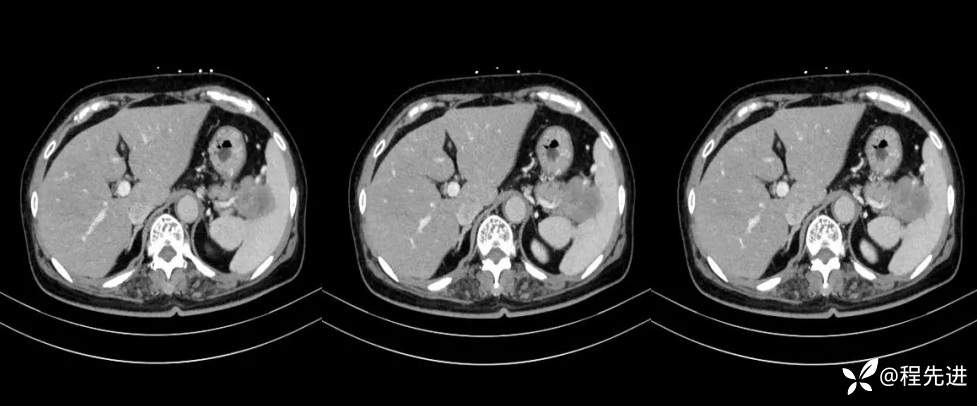

【现病史及既往史】:体检发现胰尾部肿块4年,当时手术病理提示异常增生性病变,现发现右侧顶部包块,逐渐增大,无明显感觉不适

影像检查: